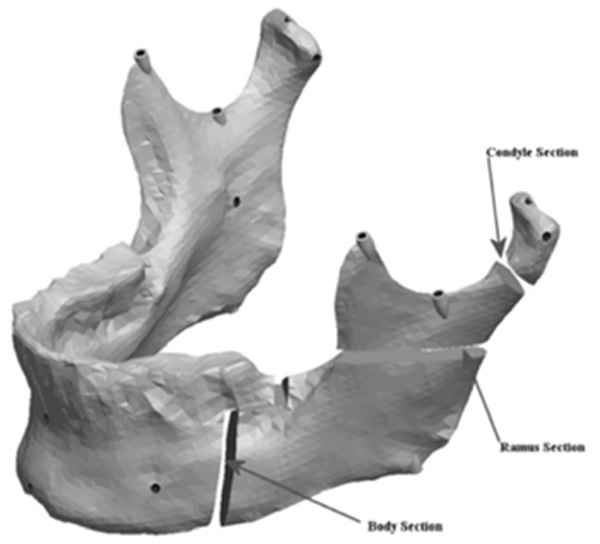

Mandible indicating the cuts for asymmetry.

The mandible halves were then re-separated and manipulated to create the remaining ranges of asymmetries. The left half of the mandible was sectioned in three areas to which the asymmetries were assigned. Fig. (7) shows the locations of the cuts made to the condyle, ramus and the body of the mandible. The Condyle section was located half way between the condylar head and the depth of the sigmoid notch. The location for the cut was determined by constructing a plane half way between the most superior point on the condyle head (Cs) and the depth of the sigmoid notch (Sn). The plane was perpendicular to the Cs-Sn line and was made straight through the neck of the condyle.

Fig. (8) depicts the location in the condylar neck for the sections made to generate the condyle asymmetries. From this section, vertical and complex asymmetries were constructed in the condylar region. The vertical manipulation created was to a maximum of 9mm asymmetry on 3mm increments and the complex condylar asymmetries were 9mm vertical and 6mm horizontal lateral asymmetry with 3mm vertical and 2mm lateral increments. Fig. (9) and Figure 10 represent images of models with vertical condylar asymmetry and models with the complex vertical and horizontal lateral condylar asymmetry respectively.

The Body section was located 43mm anterior to Cs as a plane perpendicular to the occlusal plane. The cut extended 8mm into the body before extending 10mm anterior at a 90° angle. The cut then continued vertically at 90° through the remaining body of the mandible forming a “Z-pattern” type cut. Fig. (11) outlines the location and pattern of the section made to the body of the mandible to create the body asymmetry. From this section an anteroposterior asymmetry of up to 9mm were constructed in the body region with 3mm increments. Fig. (12) represents a model with anteroposterior body asymmetry.

The Ramus section was located half way between the superior aspect of the condylar head and the depth of the antigonial notch. The location for the cut was determined by constructing a point half way between the most superior point on the condyle head (Cs) and the depth of the antigonial notch (Ag). A plane was selected perpendicular to the Cs-Ag line and plane MD which was used to guide the cut that penetrated through the neck of the condyle running parallel to the occlusal plane. Fig. (13) represents the location in the ramus of the mandible for the sections made to generate the ramus asymmetries. From this section, vertical and complex asymmetries were constructed in the ramal region. The vertical manipulation studied was to a maximum of 9mm asymmetry on 3mm increments and the complex ramal asymmetry was maximum of 9mm vertical with 3mm increments and 6mm horizontal lateral asymmetries with 2mm increments Fig. (14) and Fig. (15) represent images of models with the vertical ramal asymmetry and with the complex vertical and horizontal lateral ramal asymmetry respectively.